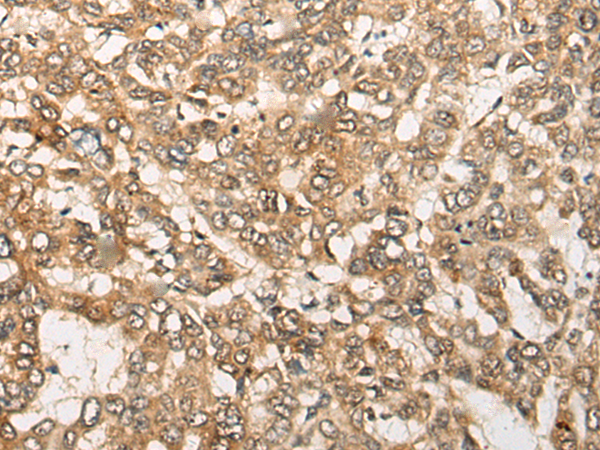

ELISA, IHC |

IHC positive control: |

Human liver cancer |

IHC Recommend dilution: |

25-100 |